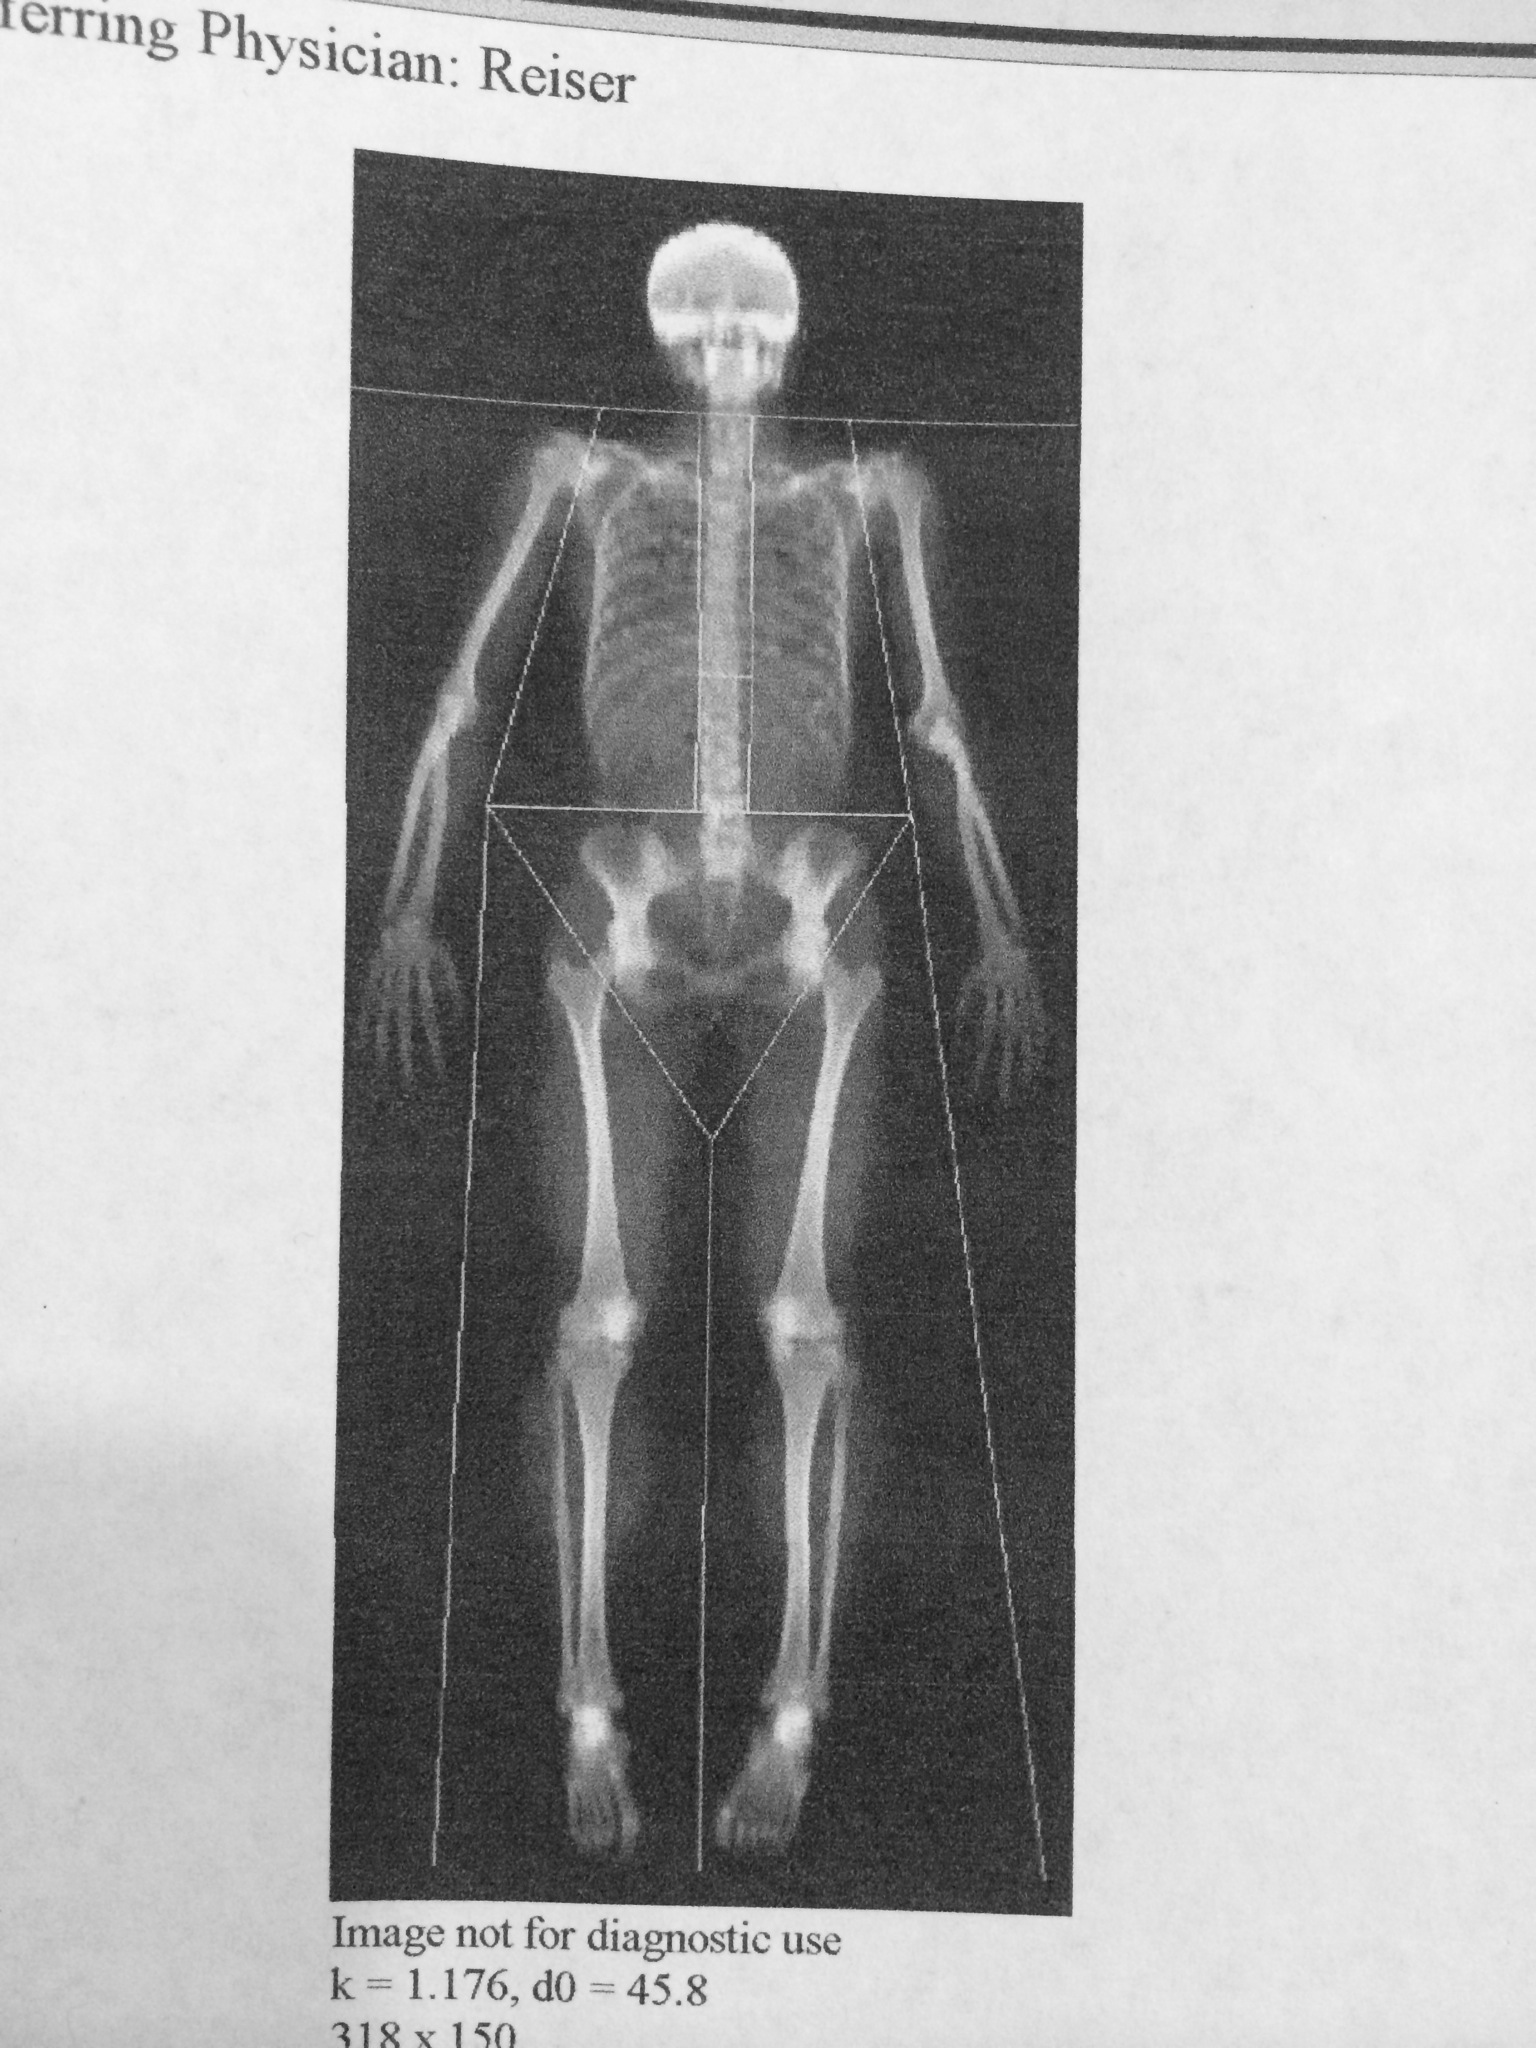

Dual-energy x-ray absorptiometry (DEXA or DXA, depending on source) is the standard for measuring bone mineral density (BMD) and to help diagnose osteopenia and osteoporosis. The scan itself is easy-peasy. You are position on a comfy table and aligned correctly. Then the scan begins and lasts about 8 minutes, and the table and x-ray emitter moves around to scan your whole body. The total radiation received is far less than a typical chest x-ray (or even hanging out in our thin-atmosphered mountains here in WY and CO!). Usually these scans are recommended for healthy women beginning at age 65, or younger if there’s suspicion or risk factors for osteoporosis.

Along with BMD, the DEXA scan also measures lean and not-so-lean body mass. Those results from today were not discussed with me as they did not want to influence the test subjects’ activities (oh us silly cyclists), but will be discussed at the August/Septemeber follow up appointment.

Seeing my skeleton is so cool!!!!